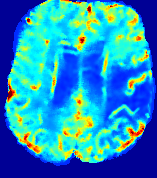

Slice #1Slice #2Slice #3Slice #4Slice #5Slice #6Dgtsuperscript𝐷gtD^{\text{gt}}Refer to captionRefer to captionRefer to captionRefer to captionRefer to captionRefer to captionDestsuperscript𝐷estD^{\text{est}}Refer to captionRefer to captionRefer to captionRefer to captionRefer to captionRefer to captionRefer to caption0.300.300.300.240.240.240.180.180.180.120.120.120.060.060.060.000.000.00(mm2/s)𝑚superscript𝑚2𝑠(mm^{2}/s)𝐕est𝟐subscriptnormsuperscript𝐕est2\|\bf{V}^{\text{est}}\|_{2}Refer to captionRefer to captionRefer to captionRefer to captionRefer to captionRefer to captionRefer to caption0.00300.00300.00300.00240.00240.00240.00180.00180.00180.00120.00120.00120.00060.00060.00060.00000.00000.0000(mm/s)𝑚𝑚𝑠(mm/s)

Figure 15: PIANO identifiability testing: diffusion imaging via advection-diffusion. Top row shows Dgtsuperscript𝐷gtD^{\text{gt}} used for simulating ground truth pure diffusion. Rows below show the estimated Destsuperscript𝐷estD^{\text{est}} and 𝐕est2subscriptnormsuperscript𝐕est2\|{\bf{V}}^{\text{est}}\|_{2} on corresponding slices. Note that the plotted value scale for 𝐕est2subscriptnormsuperscript𝐕est2\|{\bf{V}}^{\text{est}}\|_{2} is 0.01 of that for Dgtsuperscript𝐷gtD^{\text{gt}} and Destsuperscript𝐷estD^{\text{est}}.

Similarly, we test the behavior of PIANO when estimating both advection and diffusion from a pure diffusion-driven process. The goal is to determine if PIANO is able to recognize that there is only diffusion governing the given concentration time-series. We use the same ‘Diffusion Imaging’ data simulation of Sec. 4.2.1 as the concentration dataset, PIANO estimates both velocity 𝐕estsuperscript𝐕est{\bf{V}}^{\text{est}} and diffusivity Destsuperscript𝐷estD^{\text{est}}. Estimation results in Fig. 15 confirm PIANO’s identifiability again: the estimated 𝐕est2subscriptnormsuperscript𝐕est2\|{\bf{V}}^{\text{est}}\|_{2} is almost invisible compared to Destsuperscript𝐷estD^{\text{est}}, even plotted with a 1%percent11\% value range compared to that for Destsuperscript𝐷estD^{\text{est}}. On the other hand, Destsuperscript𝐷estD^{\text{est}} achieves comparable estimation performance as ‘Diffusion Imaging via Diffusion’ in which PIANO predicts Destsuperscript𝐷estD^{\text{est}} alone (shown in Fig. 13).